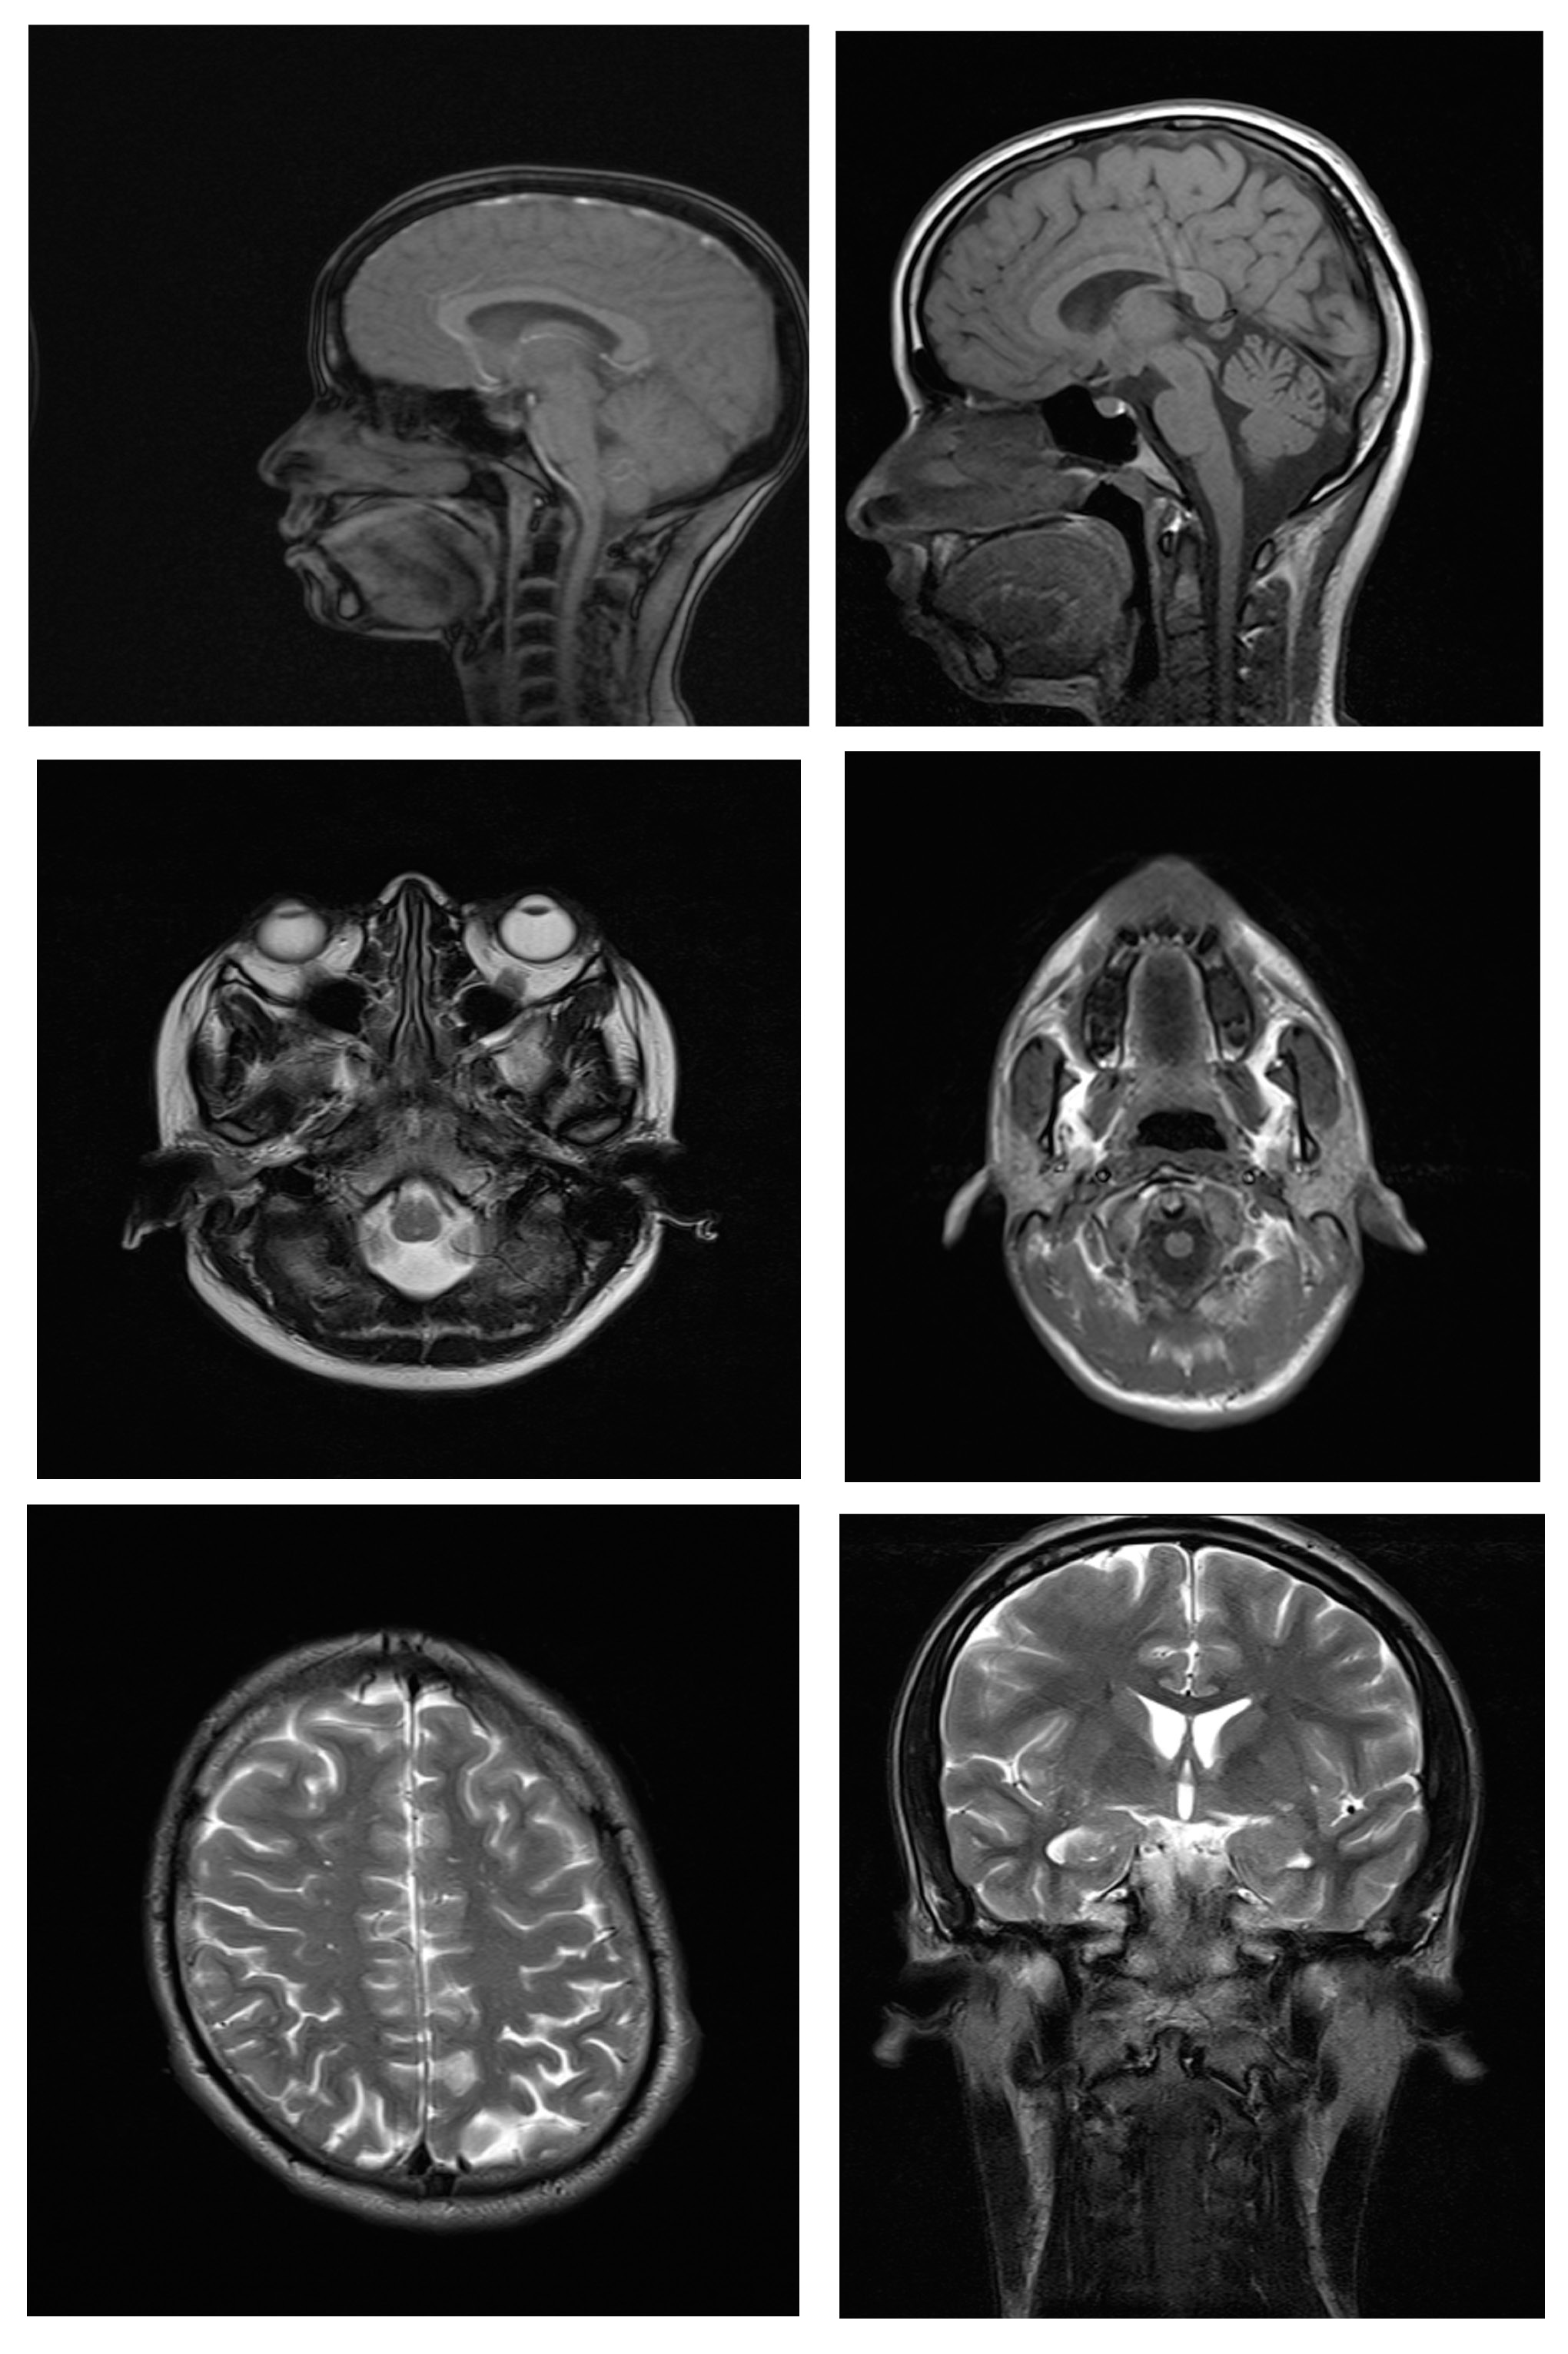

Magnetic resonance imaging scans were taken for all 38 subjects to study diagnostic image quality. Since the orthodontic appliances were securely bonded with orthodontic composite, there were no special precautions taken regarding the possible dislodgement and heating of the appliances, as previous studies had found changes in the temperature of the appliances to be clinically insignificant (within 1°C).16 The MRI scans for all types of bracket and retainer materials are shown in Figure 1, Figure 2, Figure 3, Figure 4, Figure 5, Figure 6, Figure 7, Figure 8, Figure 9, Figure 10. Non-diagnostic or unclear ROI are marked with arrows. None of the patients reported any discomfort or pain during MRI examination. The MRI scans were analyzed by a panel of 6 qualified and licensed radiologists, who assessed their diagnostic quality. The scans were compared with controls that included images from the archives of the Department of Radio-Diagnosis of Kamineni Institute of Medical Sciences. The radiologists ranked the images according to the distortion observed in the abovementioned ROI, using the modified receiver operating characteristic (ROC) analysis of distortion scoring system (Table 2), as described by Elison et al.17 In this method of distortion classification, a score of 3 represents the cut-off point for clinical usability. Images with a score of 3 have moderate distortion or artifacts, but they can still be used for diagnosis.

Ceramic self-ligating brackets with metal slots had a mean distortion score of 1.67 and mean distortion scores of 1.6 at all 6 anatomic sites except for the posterior cerebral fossa (1.0). This indicates minimal distortion for all ROI. Hence, the MR images taken with self-ligating brackets were diagnostic. A study conducted by Asano et al., in which 3 types of brackets (titanium, ceramic and ceramic with metal slots) were used in a single patient, concluded that the MR images showed little distortion and were interpretable.27 Since all 3 types of brackets were used in a single patient, one cannot distinguish their individual effects on the MRI scans.27

The mean distortion scores for ceramic and polycarbonate brackets were 1.00, and the mean distortion scores at all 6 anatomic sites were also 1.00, which implies no distortion for any ROI; hence, the MR images with ceramic and polycarbonate brackets were considered diagnostic.